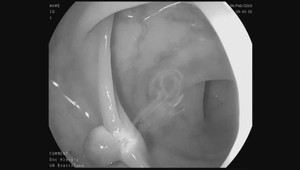

Kolonoskopia bez bolesti? Union a Dôvera preplácajú analgosedáciu, VšZP ruší limity Slovensko - aktuality